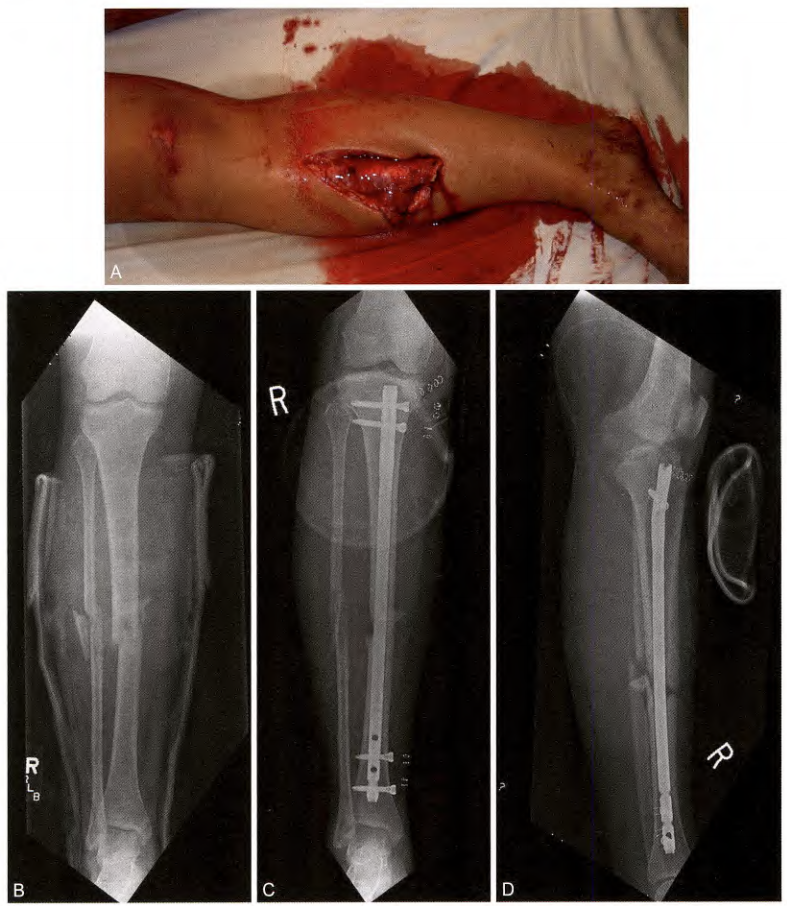

图 1. 清创和固定后伴有骨缺损的复杂 3B 型开放性胫骨骨干骨折图像。这类复杂的开放性骨折,应尽快由骨科和整形外科专家联合处理。

a 3B 型开放性胫骨临床照片,显示广泛的中段粉碎性骨折,及软组织污染。骨折的正位和侧位 X 光片。

图 1b 清创后的骨与软组织术中图像。图 1c 骨缺损的术中照片。

图2、A.伴有血管损伤的开放性ⅢB型胫骨骨折;B.X线表现;C 和 D.交锁髓内钉固定术后